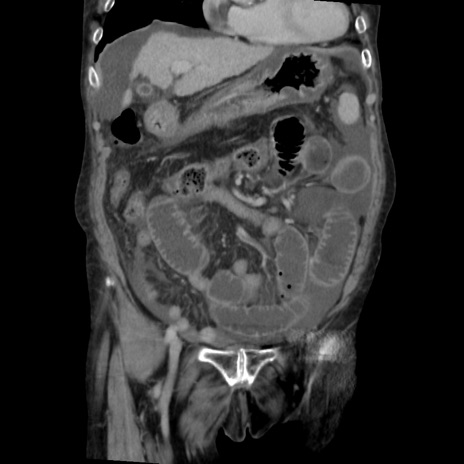

症例31(冠状断像)

矢状断像